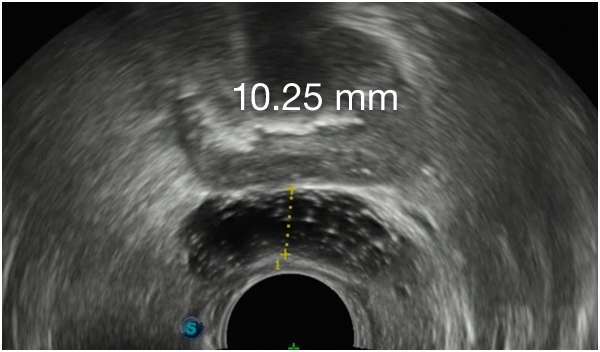

Barrigelの初回留置-連続症例(同日内)

TRUS画像提供:Daniel R. Welchons, MD

Urologist; New York, United States

DR. WELCHONSの留置テクニック